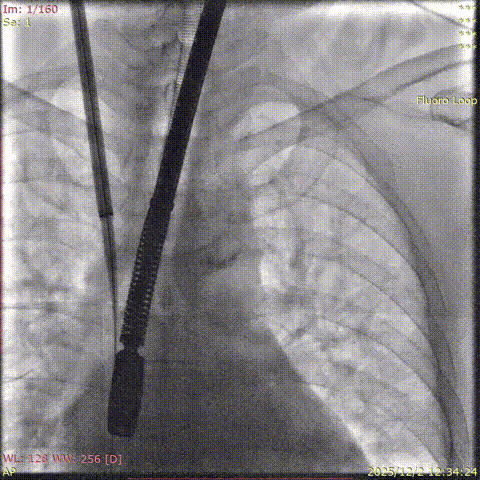

Advancement of the delivery sheath into the right atrium

Baseline coronary angiography

Post-closure angiography confirmed that the right coronary artery was not affected.

Coronary angiography after the deployment of the second clip.